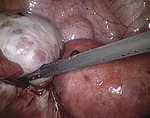

Po wytworzeniu odmy otrzewnej wprowadzono przez pępek trokar 10 mm, a następnie optykę laparoskopu i trokary boczne 5 mm. Pacjentkę ułożono w pozycji Trendelenburga. W zatoce Douglasa uwidoczniono zmieniony torbielowato lewy jajnik o średnicy około 6 cm oraz podobnie zmieniony jajnik prawy o średnicy około 5 cm (ryc. 1). Jajowody, macica oraz pozostałe narządy jamy otrzewnej dostępne wizualizacji laparoskopowej były niezmienione.